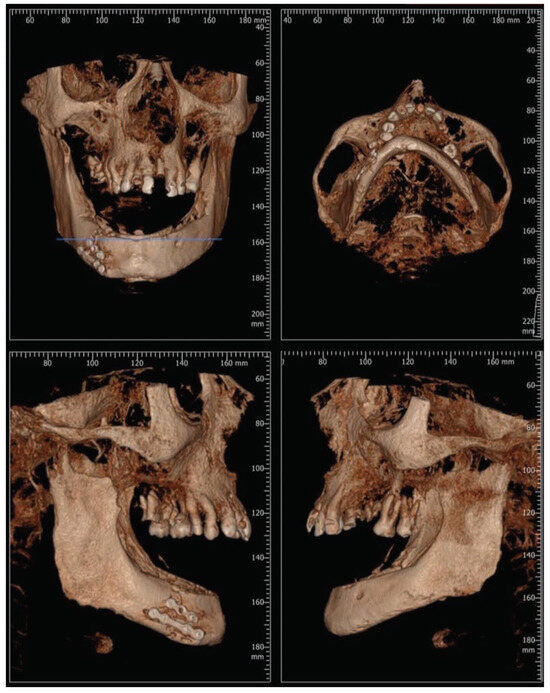

:Case Presentation